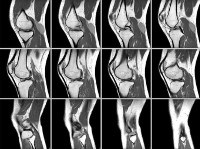

MRI of the knee joint.

МРТ коленного сустава. Метод неинвазивного диагностического обследования области коленного сустава с использованием электромагнитных волн и постоянного магнитного поля для получения послойного изображения высокой точности. Используется для выявления воспалительных и деструктивных процессов, отклонений в строении сустава, применяется в процессе диагностики поражений мениска и связочного аппарата, сложных переломов, вывихов и переломов поражений. Исследование показано для визуализации опухолей и во время предоперационной подготовки пациентов. Магнитно-резонансная томография коленного сустава является высокоинформативной безопасной процедурой, обычно выполняемой на амбулаторном уровне, она может быть нативной или контрастной.

Магнитно-резонансная томография колена использовалась в диагностических целях в течение нескольких десятилетий и является наиболее точным методом визуализации, особенно для образований мягких тканей, расположенных внутри и вокруг сустава. Изображения высокого разрешения, связанные с реакцией клеток на электромагнитное излучение. Полученный сотовый отклик фиксируется датчиками с созданием серии черно-белых изображений. МРТ коленного сустава является распространенным методом обследования в области травматологии, ортопедии и спортивной медицины, применяется при диагностике ревматологических и онкологических заболеваний.

Из-за высокой стоимости МРТ коленного сустава в Москве и регионах процедура обычно не назначается. Обследованию предшествуют рентгенография и компьютерная томография коленного сустава, а также УЗИ. Рентген и КТ используются для визуализации костной основы и частично связочного аппарата. Поэтому они широко используются для диагностики переломов, вывихов, подозреваемых случаев остеоартрита коленного сустава и других поражений. Контрастная КТ обычно назначается при подозрении на опухоль. МРТ коленного сустава чаще используется для видимых в исследовании повреждений мягких тканей.Ультразвук является одним из наиболее экономичных методов визуализации и дает представление о мягких тканях, таких как МРТ коленного сустава. По этой причине ультразвук широко используется при первичной диагностике повреждения мягких тканей и воспалительных процессов в полости коленного сустава. Кроме того, совместные операции часто проводятся под контролем ультразвука. МРТ предпочтительна, когда информация, полученная из других диагностических методов, недостаточна или когда необходимо установить точное местоположение процесса, что может быть трудно достичь с помощью ультразвука коленный сустав.